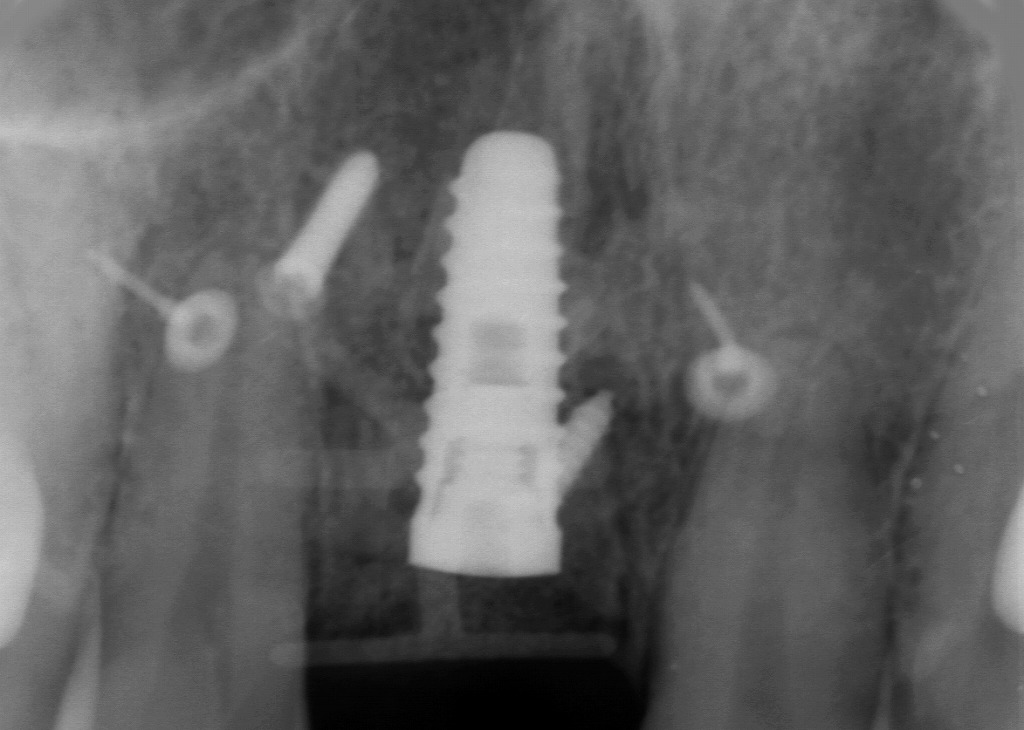

■ インプラント埋入時のデンタルX線写真

このX線画像は、右上顎1番部にインプラントを埋入した直後のデンタルX線写真です。中央の白く太い構造がインプラント体で、スレッド(ネジ形状)まで明瞭に確認できます。

左右には、自家骨ブロックやメンブレンを固定する際に使用されたGBR固定用スクリュー(4本)が描出されています。前歯部インプラントでは頬側骨が不足することが多く、この症例でも大規模な水平的骨造成が行われたことがX線から読み取れます。

■ 画像から読み取れるポイント

1. インプラントの適切な垂直位置・角度

インプラント軸は周囲歯の長軸と調和しており、審美領域に求められる自然な補綴位置を実現するために良好な方向に埋入されています。

2. 固定スクリュー(ボーンスクリュー)の位置

左右のスクリューは、

- 自家骨ブロックの固定

- メンブレンの安定化

のいずれかに使用されており、これにより骨造成スペースを確実に保持しています。

3. 根尖部までの安全性

インプラント先端が鼻腔底や切歯管に接近しすぎておらず、解剖学的に安全な範囲内で埋入されていることが確認できます。

■ 臨床的まとめ

- 前歯部の骨量不足に対し、インプラント+大規模GBRを組み合わせた高難度症例である。

- 術直後のX線として、インプラント体の位置・角度・周囲固定物が適正であり、成功につながる理想的な初期状態を示している。

- この後の治癒によって、スクリュー周囲の骨再生がどれだけ進むかを評価し、二次オペへと移行していく。